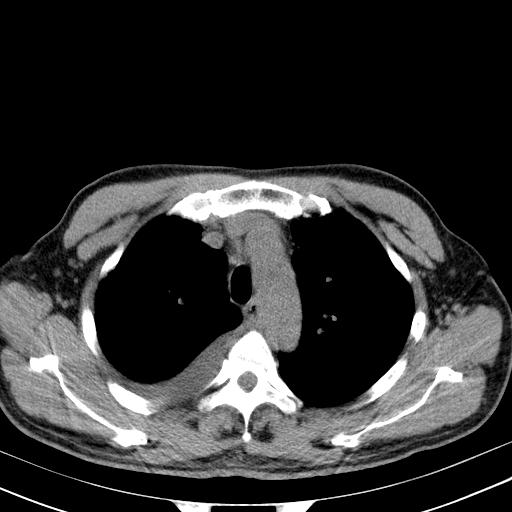

以下是引用zjzjr在2010-3-21 17:39:00的发言:[br]右下中心型肺癌并阻塞性肺炎/不张,纵膈淋巴结肿大,右侧大量胸腔积液,左侧少量胸腔积液

以下是引用zxl51642在2010-3-21 17:06:00的发言:[br]右下中心型肺癌并阻塞性肺炎/不张,纵膈淋巴结肿大,右侧大量胸腔积液,左侧少量胸腔积液,少量腹水。建议纤维支气管镜进一步检查。